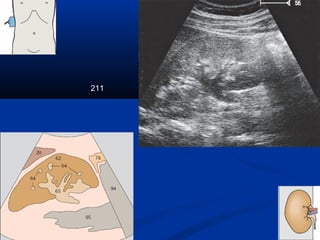

211